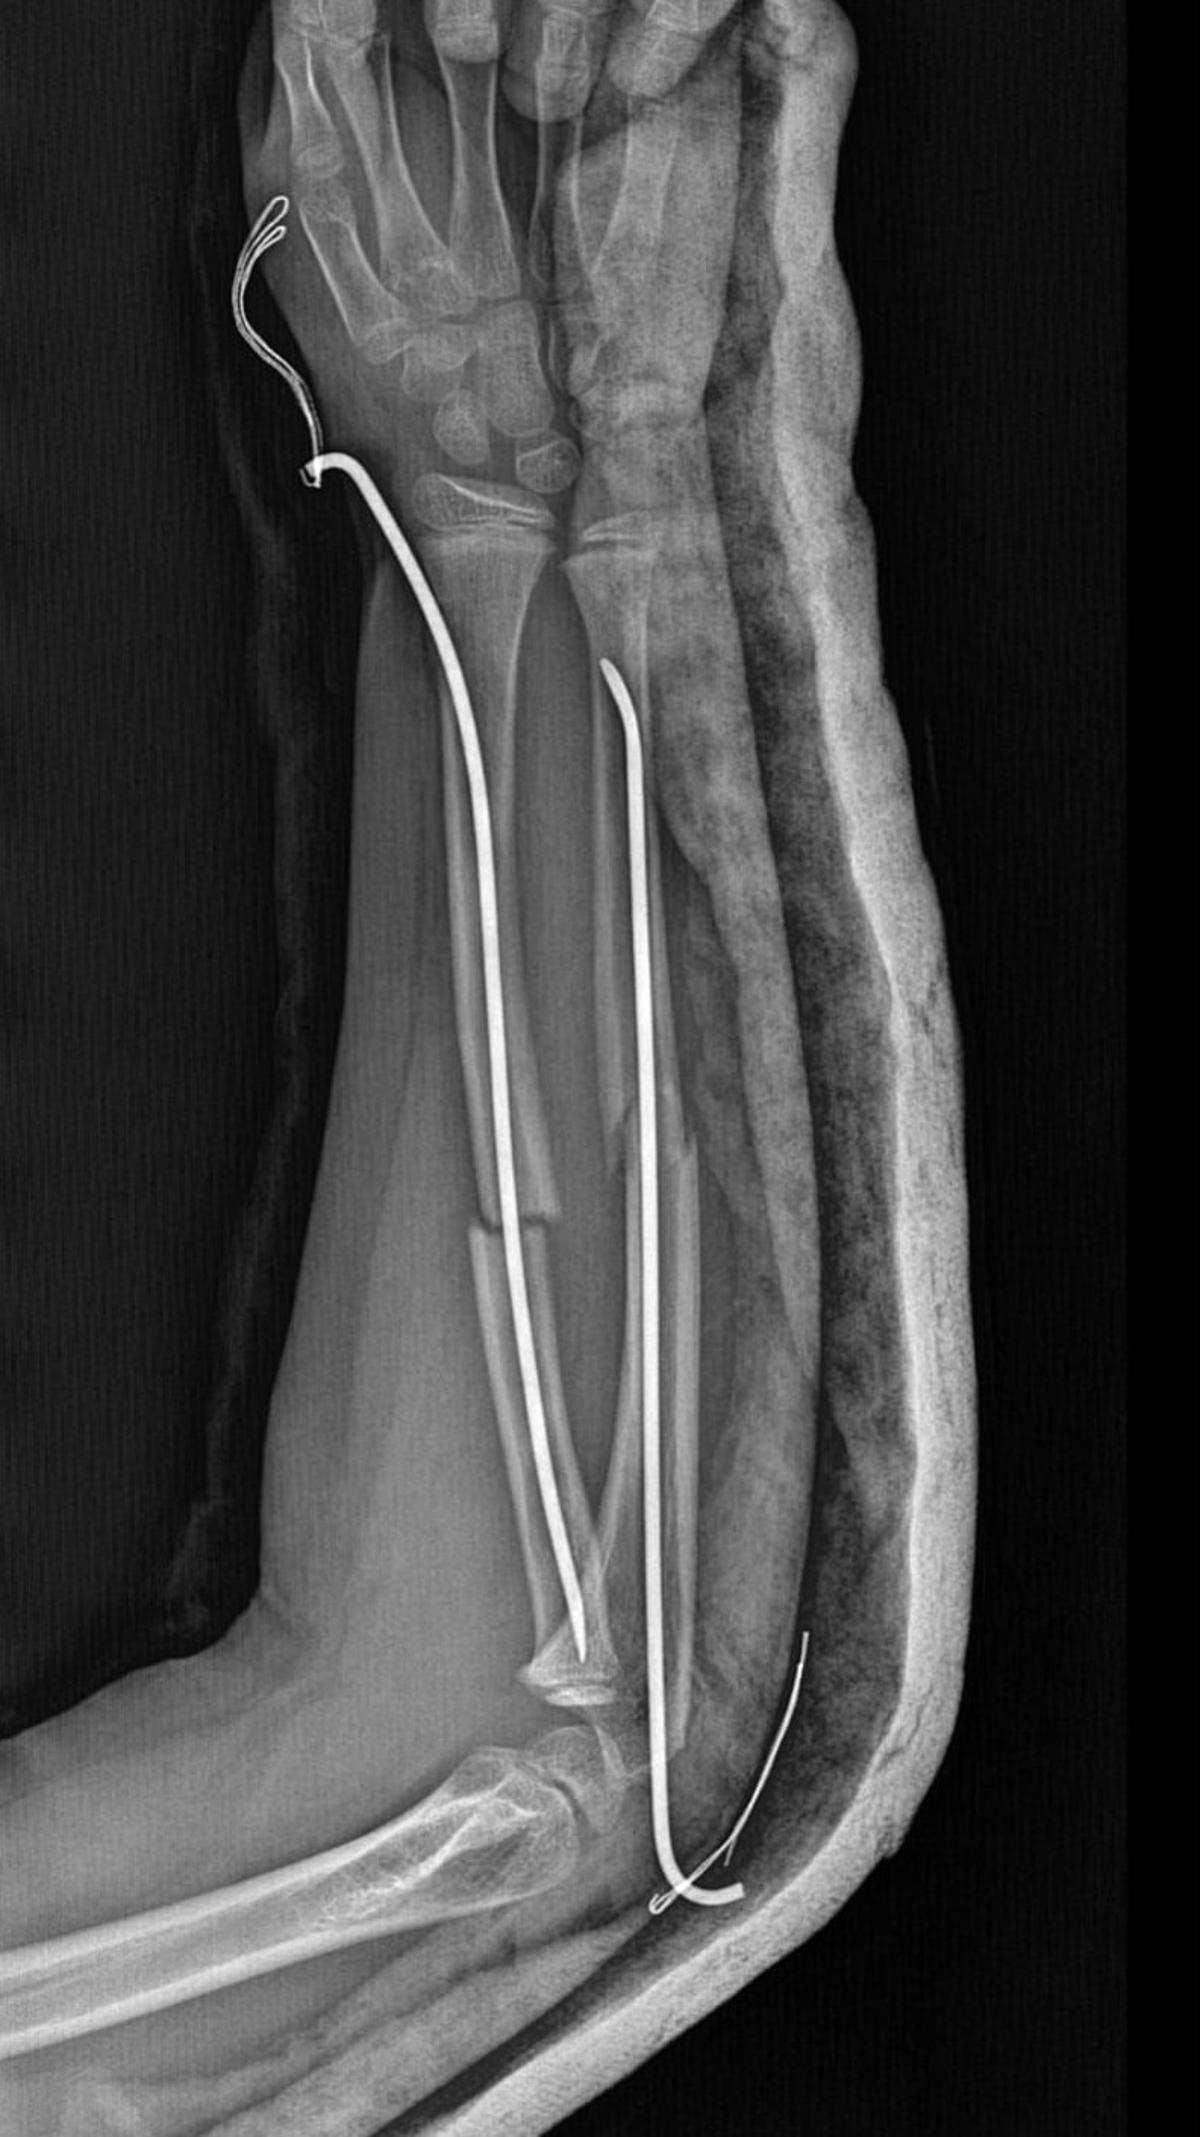

Olay, geçtiğimiz ay Büyükçekmece Tepecik'te bulunan bir ilkokulda meydana geldi. İddiaya göre 8 yaşındaki Y.K.Ş. okulda bir süredir kendisini rahatsız eden 9 yaşındaki çocuk tarafından darp edilerek kolu ikiye katlandı. Y.K.Ş.'nin 2'ye katlanan kolu 2 ayrı yerinden kırıldı. Öğretmenler Y.K.Ş.'nin ailesini arayarak, 'oğlunuz arkadaşıyla kavga etti duvara çarptı' denildi. Oğlunu okuldan alıp hastaneye götüren anne Songül Gökdemir, oğlunun kolunun 2 ayrı yerinden kırıldığını öğrenip ameliyata alınacağını duyduğunda büyük şok yaşadı. Konuyla ilgili anne Gökdemir savcılığa giderek şikayetçi oldu. Savcılıktan ise 'söz konusu Suça Sürüklenen Çocuğun yaşının 12'den küçük olduğu gerekçesi ile kovuşturmaya yer yoktur' kararı çıktı. Anne Gökdemir karara itiraz ederken mağdur Y.K.Ş. ise haftalardır okula gidemiyor. Eğitimi aksayan çocuğun 2 hafta sonra ise platinlerinin çıkarılması için yeniden ameliyata gireceği öğrenildi.

Yaşanan olayı anlatan Songül Gökdemir, " Arkadaşlarından darbe aldığını biliyordum. Ayrıca Eylül ayından bu yana bir arkadaşının onun kolunu kırmaya çalıştığını söyledi. Ben de 'arkadaşını öğretmene söyle' dedim. Bundan kaçıyordu. O gün de rehber öğretmenine bu arkadaşını şikayet ettiler. Ben işe gittim 1 saat sonra öğretmeni aradı. Oğlunuz arkadaşıyla birbirini itekledi kolunu duvara çarptı gelir misiniz ?' dedi. Kendi imkanımla hastaneye götürdüm. Okula gittiğimde de oğlum derste oturuyordu. Öğretmen ders işliyordu ambulans çağırılmamış. Hastanede kolunda 2 tane kırık olduğunu acilen de ameliyata girmesi gerektiğini öğrendim. 3 gün sonra ameliyata alındı. Kolundaki platinlerden dolayı her gün pansumanı var. 2 hafta sonra tekrar ameliyatı var" dedi.